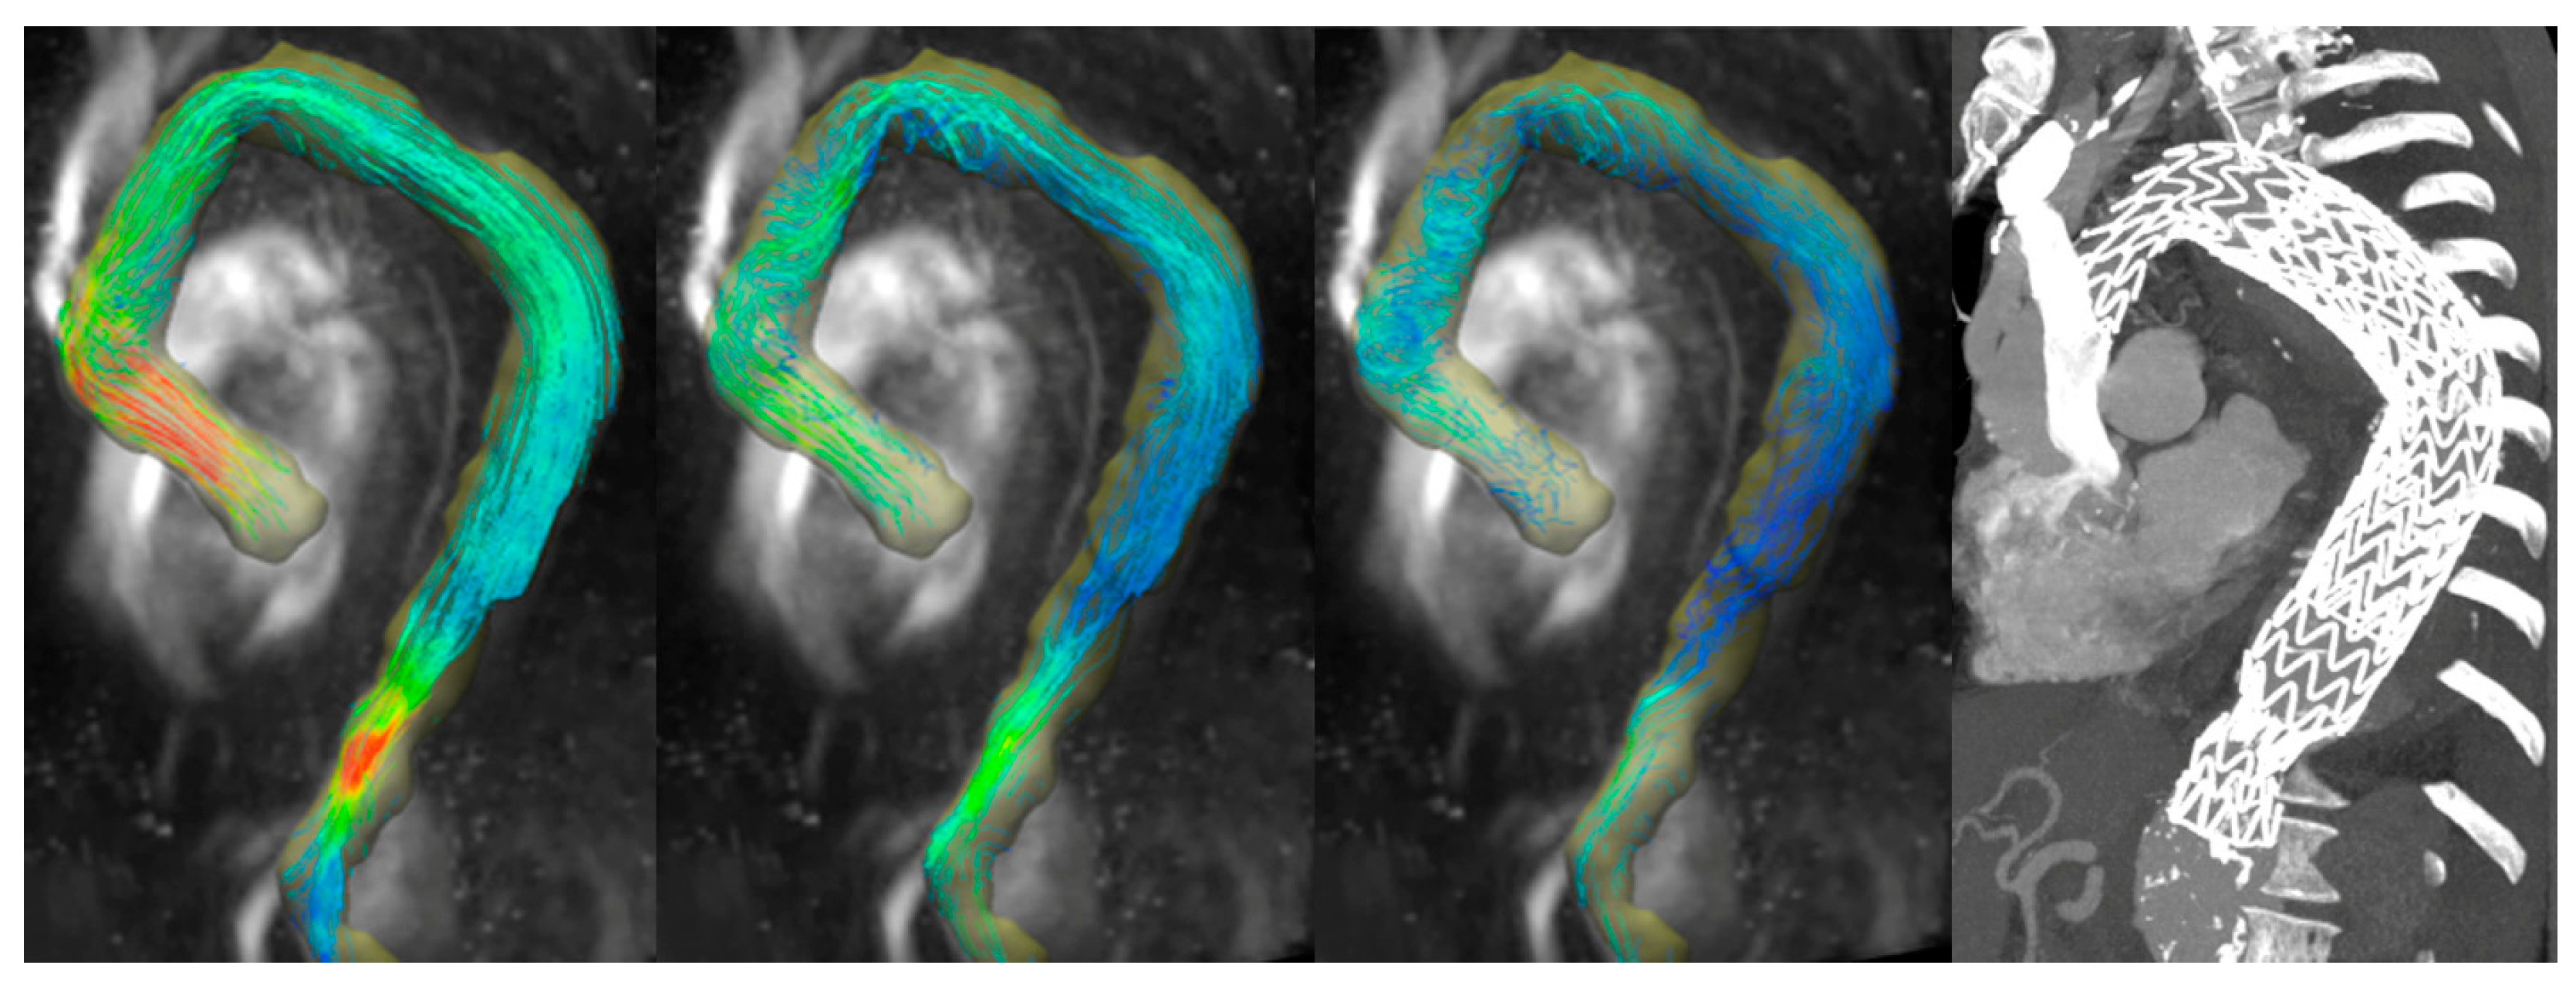

Four-Dimensional Flow MRI for the Evaluation of Aortic Endovascular Graft: A Pilot Study

3. Results